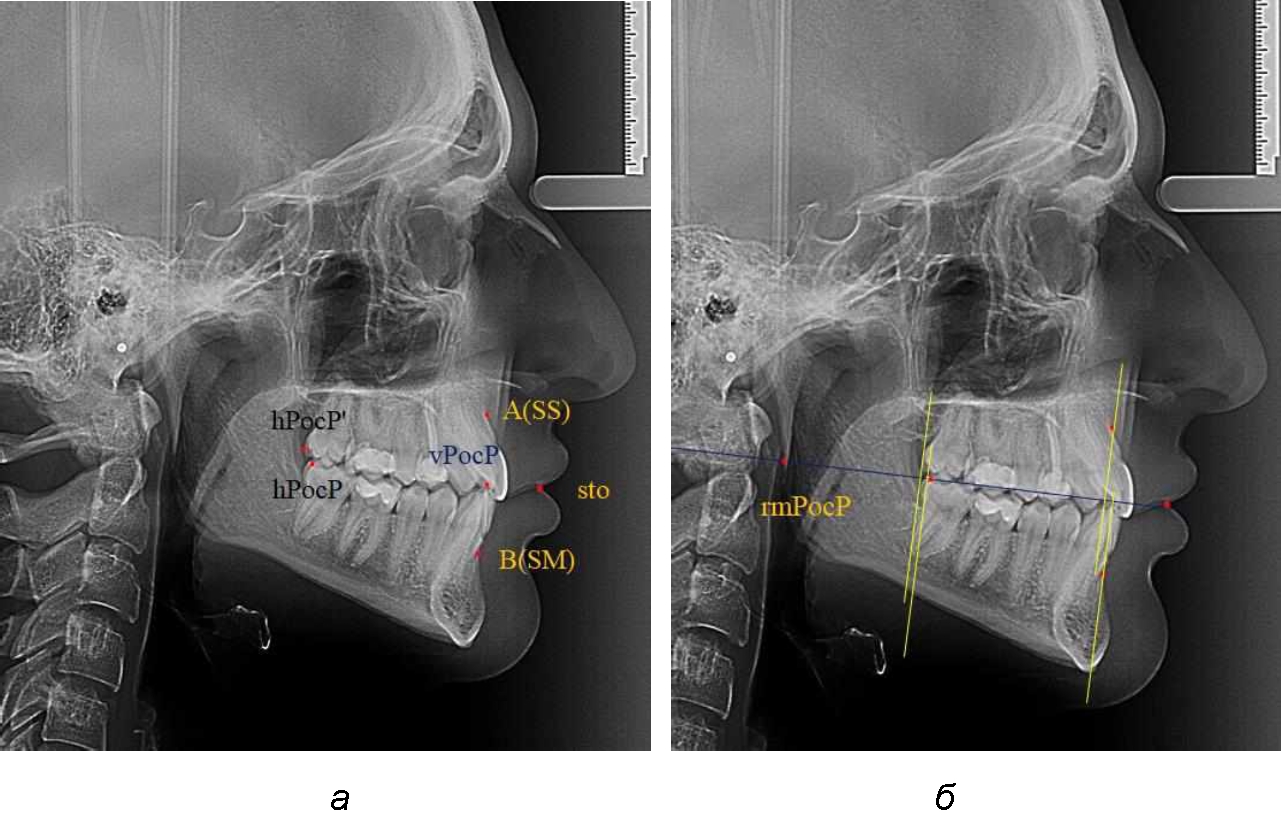

На рентгенограммах устанавливали точки Downs. На верхней челюсти субспинальная точка A(SS) располагалась в наиболее вогнутой точке альвеолярного отростка по переднему его краю. На нижней челюсти супраментальная точка B(SM) соответствовала месту наибольшей вогнутости переднего края альвеолярной части. Окклюзионную линию проводили через контактную точку резцов (vРOcP) и дистальную точку окклюзии второго нижнего моляра (hРOcP). Место пересечения окклюзионной линии с дистальным краем ветви нижней челюсти (ramus mandibule) обозначали как «rmРOcP». Перпендикулярно к окклюзионной плоскости проводили линии из точек «А(SS)» и «В(SМ)», что определяло их проекцию на окклюзионную линию. Аналогично отмечали положения дистальных окклюзионных точек верхней и нижней челюсти (рис. 1).

Рис. 1. Положение основных точек (а) и линейных ориентиров (б) для анализа положения и размеров челюстей

Альвеолярно-дентальный размер верхней челюсти и нижней челюсти оценивали по окклюзионной линии между вертикалями, ограничивающими исследуемые челюсти. Положение верхней челюсти оценивали по величине размера «rmOcP-А», а нижней челюсти по расстоянию «rmOcP-В». Линия смыкания губ обозначалась как точка «sto», вблизи которой проходила окклюзионная линия. Данный ориентир позволял провести окклюзионную плоскость при аномалиях положения резцов в вертикальном направлении, когда была сложность определения резцовой окклюзионной точки (vРOcP).